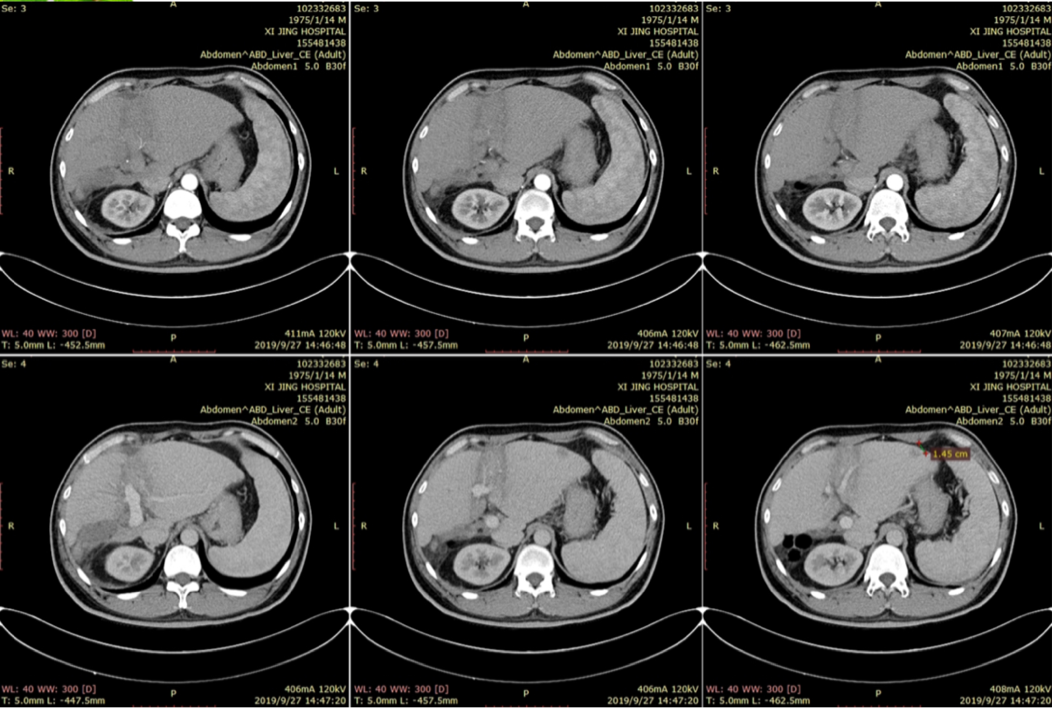

2019-09-27

2019-09-30,PET-CT